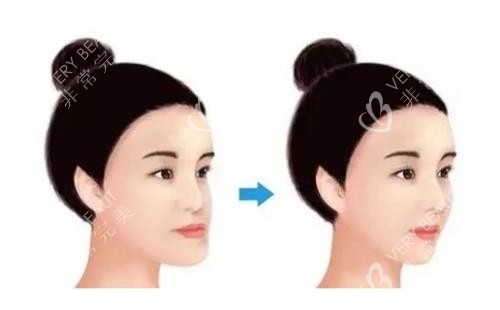

我是阿G,28岁的平面设计师,曾经因为下颌突出被同事调侃“侧脸像弯月亮”。近段日子翻相册,发现自己拍照永远只敢露正脸——直到在广州广大整形医院做完双颚手术,才敢把侧颜照设成朋友圈封面。

术后1周拆线,罗医生用棉签轻压伤口:“愈合得比较好,没感染。”回家后每天用漱口水清洁口腔,2周能吃软面条,1个月啃苹果,3个月朋友见我都问“你是不是瘦了?”——其实是下颌线出来了,脸看着小了一圈。

现在术后1年,拍侧脸照终于不用找角度,连妈妈都说:“早知道结果这么自然,当初不该拦着你。”对比小琪的修养过程,她术后5个月还有轻微不对称,而我的咬合完全正常,笑起来牙龈也不暴露了——这大概就是“医生经验”的差别吧。